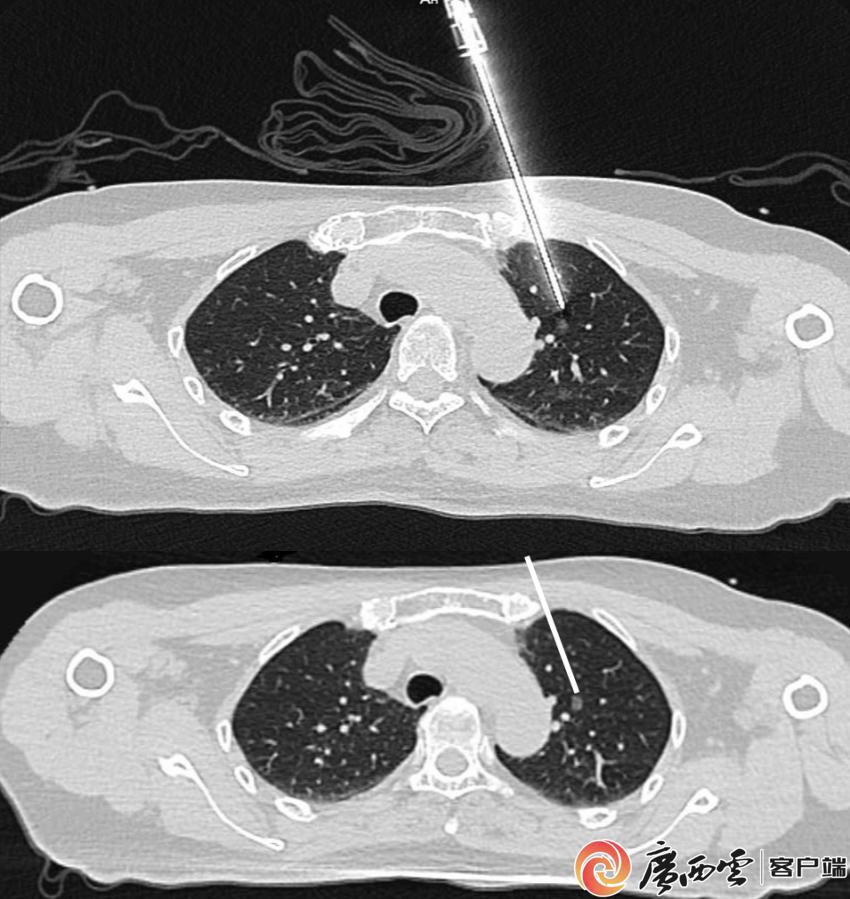

上图为实际穿刺针路径,下图白色线条为规划穿刺路径,二者高度一致。中山大学附属第一医院广西医院心胸外科供图 据介绍,目前采用的机器人穿刺手术导航定位系统,融合了CT影像与智能传感一体化技术,突破了传统电磁导航与光学导航的局限,具有定位精准、耗时短、固定稳靠等特点。仅需一次扫描即可完成患者坐标与定位系统坐标的配准,结合预设手术路径规划,系统即可引导穿刺器械精准到位。整个操作流程省去了患者体表粘贴标识、测绘穿刺点及“分步进针”等环节,大幅提升效率,也减轻了因反复调针给患者带来的疼痛与创伤。 “随着肺结节患者数量不断增加,临床对高效、安全、舒适、低辐射穿刺技术的需求日益突出。新一代穿刺机器人的引进,是对传统穿刺技术的重要革新。”刘振国表示,此次将该机器人系统应用于肺结节穿刺,也是中山大学附属第一医院总院胸外科前沿技术与先进设备向区域医院同步输出的生动体现,对推动广西肺结节精准诊疗水平的提升具有重要意义。 |